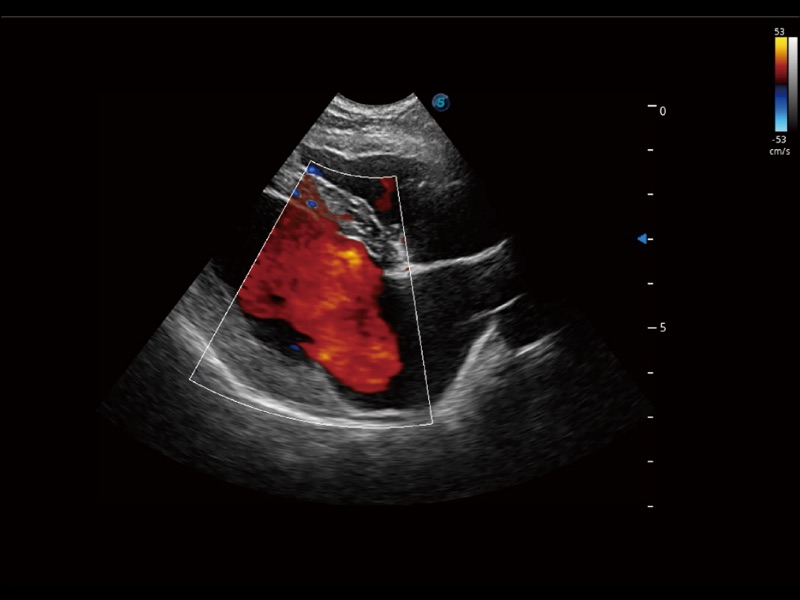

采用红、橙、黄、绿、青、蓝、紫这七种肉眼最为敏感的色彩,直观地显示组织内血流灌注的时间先后信息,更精准捕捉血流灌注走行细节。

通过创新的 Matrix E自适应滤波器和超长时间域算法,极大提升超低速微细血流的检出能力,同时更精准地滤除软组织和噪声信号,为兽用医生提供以往无法通过常规血流获得的疾病诊断信息。

通过色彩血流和实时宽景相结合,可观察到完整的静脉或动脉的血流,方便医生检查。实时扫查过程中,如有任何操作失误也可以很容易地进行回扫擦除,而不会中断扫查。

实时用颜色表示心肌组织运动,观察和定量组织的运动情况,对快速检测与评估心肌的灌注和活性、电传导及心肌收缩和舒张功能等均能提供重要的诊断信息。